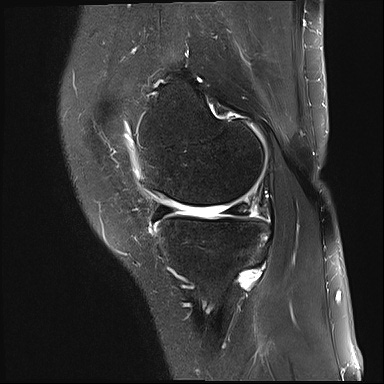

무릎 연골 손상 진단법

X-ray 촬영을 먼저 시행하고,

좀더 정확히 평가하기 위해 MRI을 통해 관절 연골면의 상태를 확인합니다.

더 자세한 상태를 확인하기 위해서 관절내시경을 통해 확인할 수 있습니다.

수술 전 MRI

2022.04.19